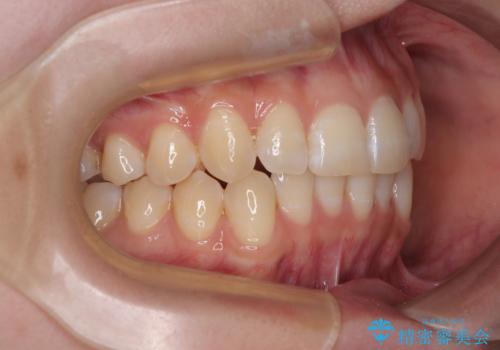

- 上下前歯の重なりを気にして来院された患者様です。

安価なインビザラインパッケージを用いての治療を希望されており、デコボコの程度が中等度であったため、インビザライン・モデレートを用いて矯正治療を行うこととしました。

インビザライン・モデレートは、製作できるアライナーの枚数に制限があるため、移動可能な量に限りがあるものの、インビザライン・ライトよりも枚数が多いため、幅広い症例に対応可能です。